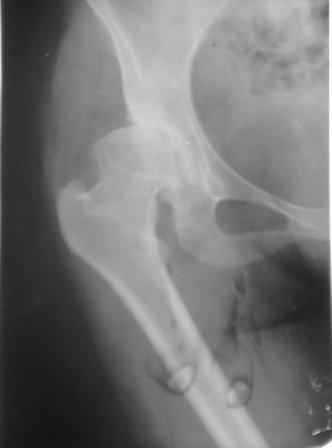

Представляю Р-снимки: обзорная, с отведением и с приведением.

Глубокоуважаемый Абдурашид. Здесь нет снимка с отведением. Если Вы сами сходили в рентгенкабинет и лично отвели пораженную конечность максимально возможно, а также дали максимально возможную внутреннюю ротацию-это одно!!!! Значит у пациентки тяжелейшая приводящая контрактура тазобедренного сустава!! И необходимо разобраться-миогенная или артрогенная? Если же Вы просто назначили указанный снимок и доверили произвести укладку рентгентехнику-это другое!!! Одному богу известно, что она делала, ведь на р-снимке отведения нет!

Все предыдущие корреспонденты предлагают вам достаточно простую вещь-смоделировать предлагаемую Вами операцию (т.е. дать отведение и внутреннюю ротацию) и посмотреть, как изменятся соотношения в суставе. Не обижайтесь, но судя по представлению клинического случая угловые величины, характеризующие пространственные соотношения в тазобедренном суставе, ваши рентгенологи не считают.

Уважаемый Игорь Владимирович. диссертации М М Камоска, и В Е Баскова я нашел, но почему-то не могу открывать, и еще в данном случае имеется дисплазия т/б за счет недоразвития крыши в/впадины да и всей подвздошной кости, маргинального вывиха или латеропозиции головки вследствие лечебных ощибок нет, головка стоит на месте. Р-граммы сделал сам, но почему-то у больной отведение и внутренная ротация стали очень болезненной, и сухожилия приводящих мышц сильно натягивается.(контрактура артро-миогенная).

Глубокоуважаемый Игорь Владимирович! Признаюсь допустил ошибку, из-за напряженности работы и нехватки времени, когда повторно внимательно посмотрел все понял и не успел исправить ошибку до Вашего поста, конечно скошенность крыши в пределах 40гр,часть головки кнаружи линии Омбредана-Перкинса , облитерация дна вертлужной впадины и т.д.-это ДМВБ.